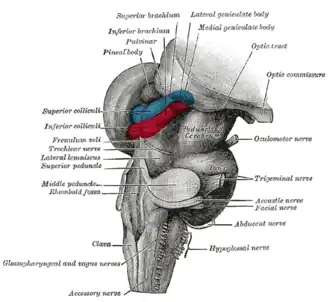

Superficial dissection of brain-stem. Lateral view.

Superficial dissection of brain-stem. Lateral view. -